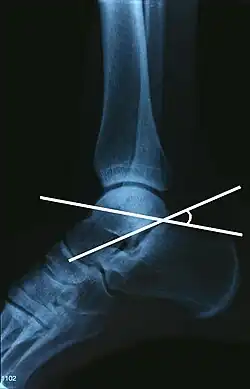

Om de hoek van Böhler te verkrijgen worden op een laterale enkelfoto, waarop de malleolus medialis en malleolus lateralis over elkaar projecteren, twee lijnen getrokken. De ene lijn loopt van de bovenste rand van de tuberositas posterior van de calcaneus naar de apex van het achterste deel van de articulus subtalaris (gewricht tussen calcaneus en talus), de andere wordt getrokken van deze apex naar de processus anterior van de calcaneus. De kleinst mogelijke hoek die deze lijnen maken, wordt de hoek van Böhler genoemd.